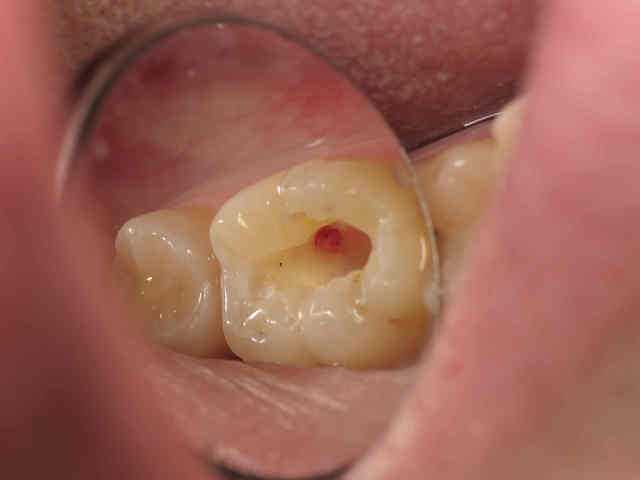

Au niveau de la corne pulpaire testée il y a cicatrisation et apposition de dentine néosynthétisée.La dent est alors stable dans le temps, je dois avoir une ou deux photos sous la main...

C2 ylzwvj - Eugenol